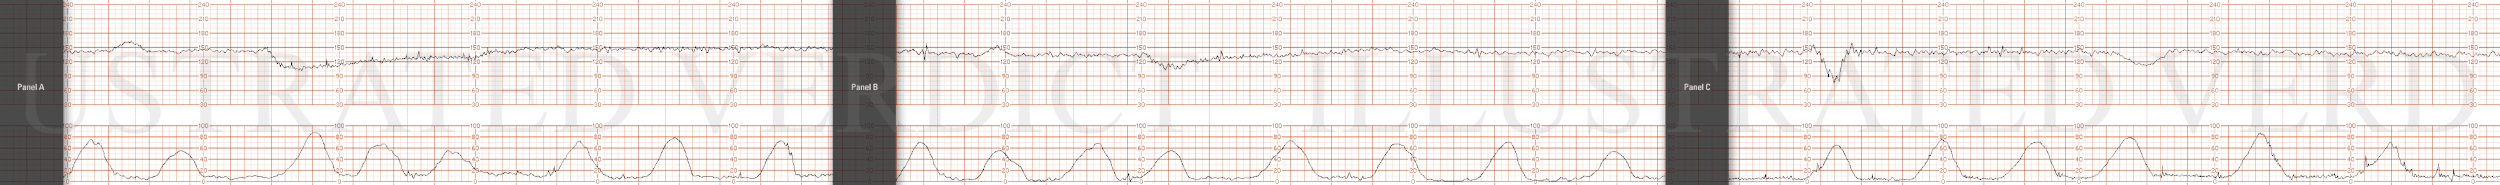

STRIP 70

1. 1st panel:

Tracing to show 140 bpm with average variability and no decelerations. Five 50-second contractions noted in 20 minutes of observation. (1st and 2nd contraction 10sec less, 5th 30secs less

2nd panel:

Panel: 20-minute of FHR strip.

Contractions:11 in 20 minutes, each lasting +/- 50-55 seconds. (1st 3rd, 4th, 6th, 7th, 8th, 10th and 11th too long 10-15 secs off)

Baseline +/- 165 bpm with minimal variability

Four mild to moderate, (but not unusual variable decelerations down to range of 105 to 125 bpm at minute 4, 11, 17 minutes, each with duration varying between 25-35 seconds.- with prompt return to baseline. There is no progression in depth or duration of decelerations – random. (1st 2nd more abrupt, 1st deeper, 4th more abrupt and deeper)

There are no spontaneous accelerations.

Indicate scalp stimulation at minute 18 with no resultant acceleration